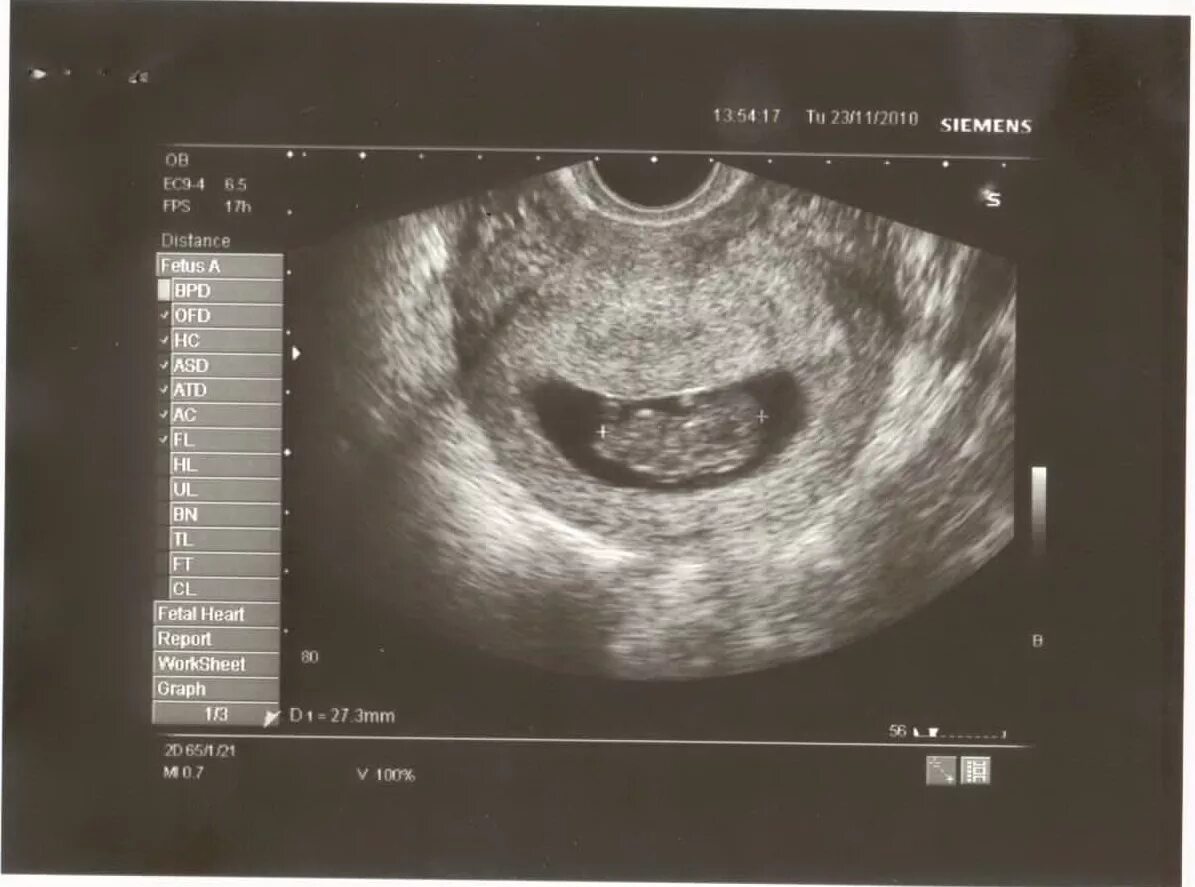

Матка 10 недель